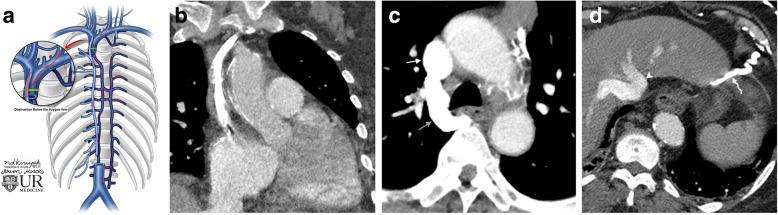

In the healthy patient, blood returns to the heart via classic venous pathways. Obstruction of any one of these pathways will result in blood flow finding new collateral pathways to return to the heart. Although significant anatomic variation exists and multiple collateral vessels are often present in the same patient, it is a general rule that the collateral pathways formed are a function of the site of venous blockage. Therefore, knowledge of typical collateral vessel systems can provide insight in localizing venous obstruction and characterizing its severity and chronicity. In addition, knowledge of collateral anatomy can be essential in interventional procedural and/or surgical planning, especially when placing catheters in patients with venous blockage. In this pictorial review, we provide a systematic approach to understanding collateral pathways in patients with venous obstruction in the upper body.

在健康患者中,血液通过经典静脉途径回流至心脏。这些途径中任何一条受阻都会导致血流寻找新的侧支途径回流至心脏。尽管存在显著的解剖变异,且同一患者体内常存在多条侧支血管,但一般规律是,形成的侧支途径取决于静脉阻塞的部位。因此,了解典型的侧支血管系统有助于定位静脉阻塞并判断其严重程度和慢性化情况。此外,了解侧支解剖结构对于介入操作和/或手术规划至关重要,尤其是在为静脉阻塞患者放置导管时。在本图文综述中,我们提供了一种系统方法,用于理解上身静脉阻塞患者的侧支途径。